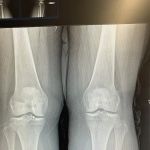

- Spinal Health Assessment: Conducting thorough evaluations to understand the root causes of pain and discomfort, often involving physical examinations and potentially imaging.